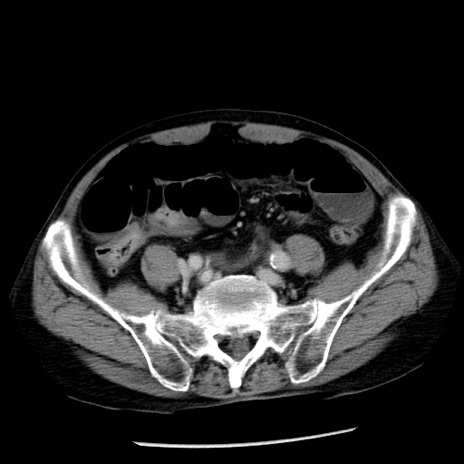

症例26(横断像)

【症例】80歳代男性

【主訴】嘔吐

【現病歴】昨晩2回嘔吐あり、今朝になっても嘔吐あり。来院。

【既往歴】胃潰瘍

【身体所見】意識清明、BT 37.6℃、BP 166/95mmHg、HR 100bpm、SpO2 97%、腹部:平坦・軟、腸蠕動音聴取良好、圧痛なし。

【データ】WBC 21900、CRP 1.46